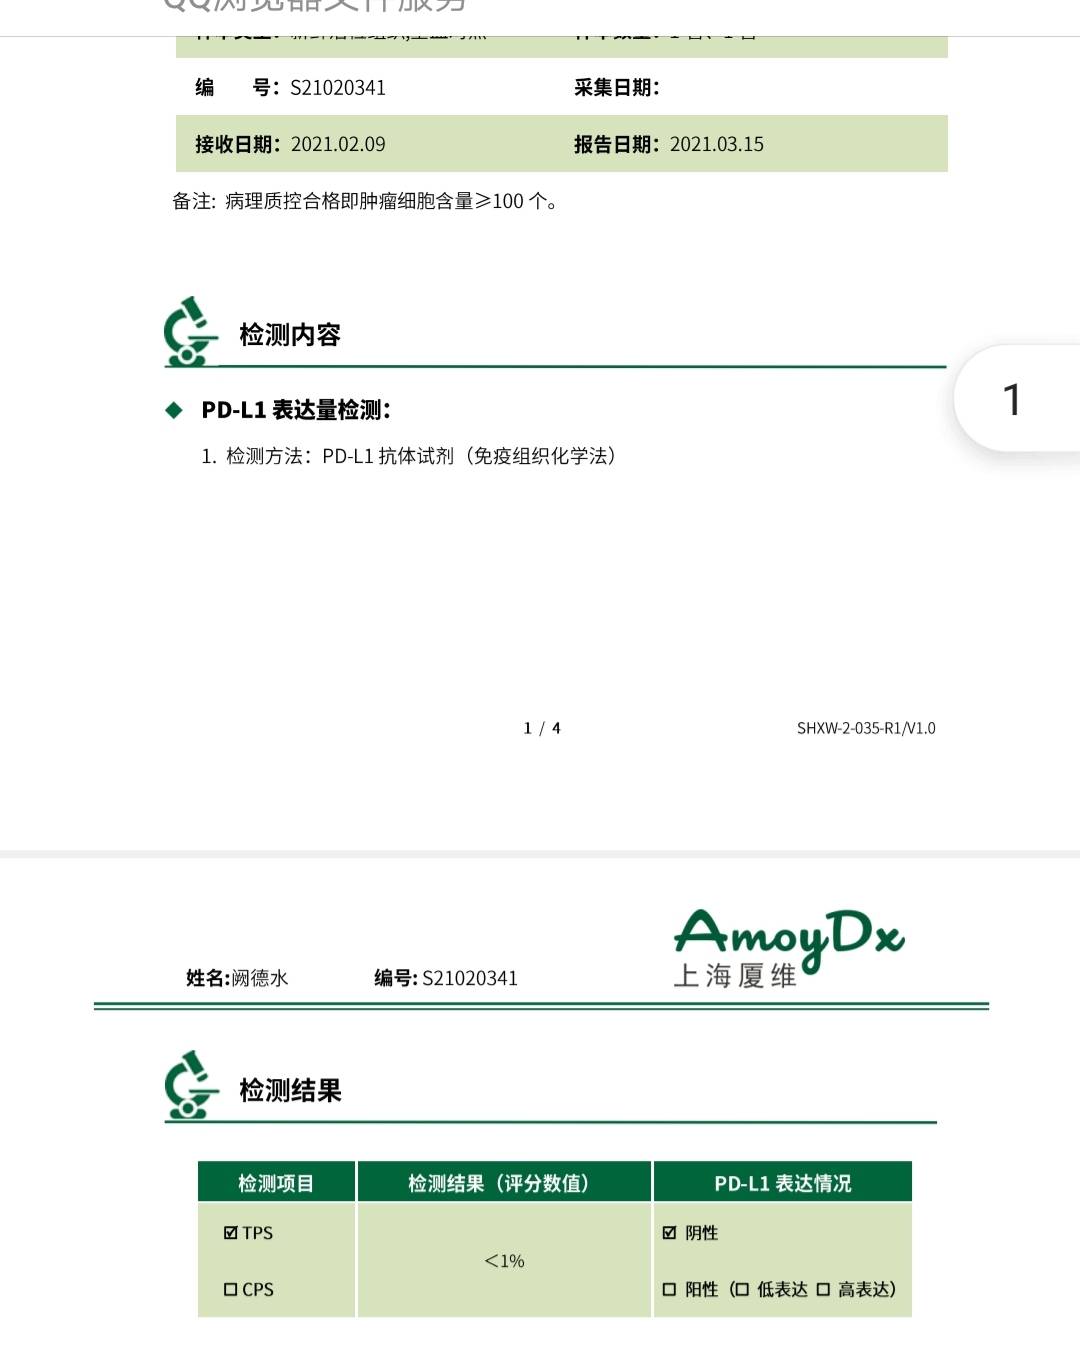

患者穿刺小标本PDL1低表达,无敏感用药的基因突变

术前新辅助时间短,且PDL1表达阴性,加入免疫能发挥作用嚒?

陈某某跟她说,术前加入免疫,激活免疫系统后能有识别肿瘤抗原的过程,如果术前没用PD1,就算术中大标本测出PDL1高表达,术后再用的话,因为肿瘤都切除了,免疫系统识别肿瘤抗原的过程就不充分,怕效果不好。

于是就在第2周期和第3周期在含铂双药化疗的基础上加入了PD1,鳞癌,选国产替雷。

术前小标本如果测出PDL1表达率低或者阴性,术前新辅助化疗完全可以积极尝试联合免疫PD1,通过疗效和病灶缩小时间,程度来判断推测免疫治疗是否有效。